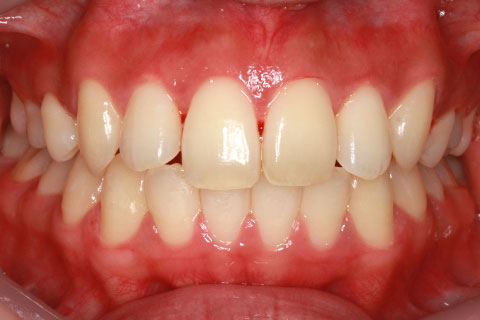

矯正期間18ヶ月

ハーフリンガル矯正2(上の歯のみ舌側矯正で治療)

治療前

治療中

治療後

- 年齢・性別

- 23歳女性

- 治療期間

- 1年6ヶ月

- 抜歯

- 上顎4番

- 治療費

- 110万円(税込み)

- 備考

- ハーフリンガル矯正

- 治療内容

- 上下前歯部凸凹の改善

- 施術の副作用(リスク)

- 裏側矯正の特性上、表側矯正と比較すると治療期間が長くかかる場合が多い。